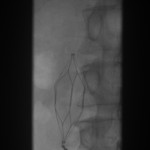

- Frontal abdominal fluoroscope: The filter is snared, ready for collapse.